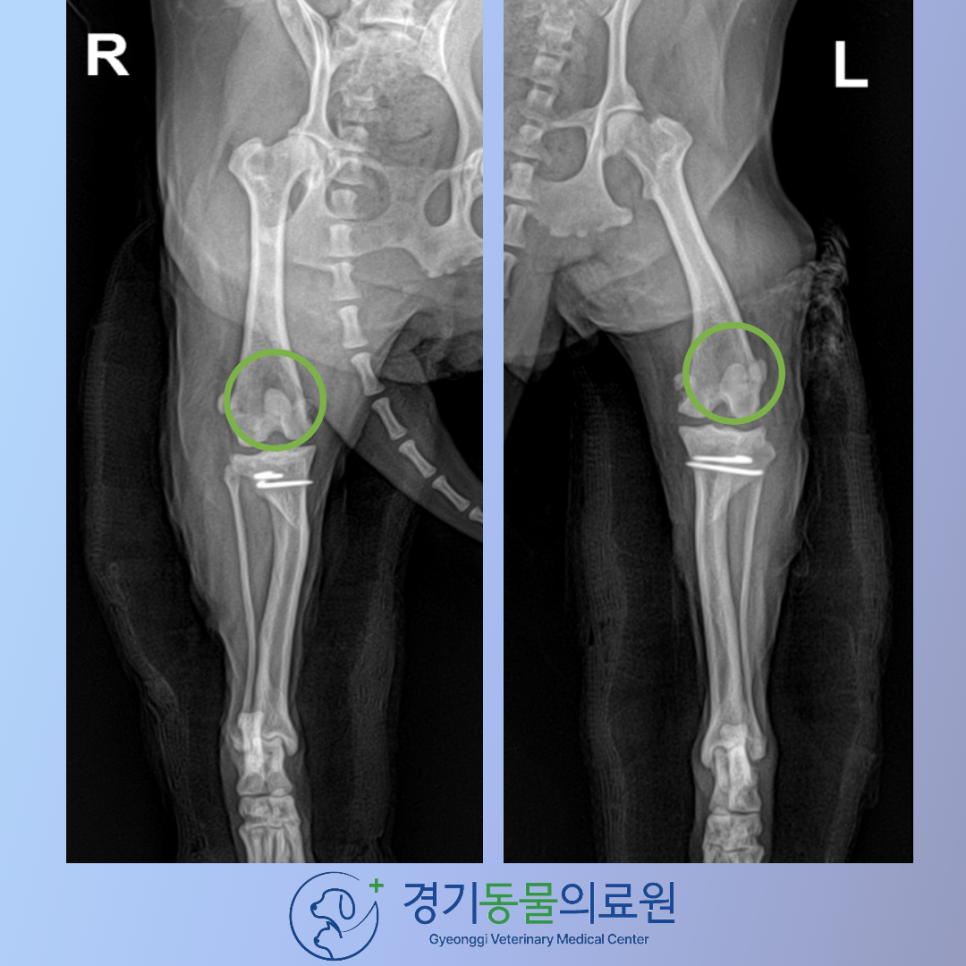

60bda69590ed4612c7dc7ca51840d198_1769113628_1753.png

수술 직후 X-ray 검사 화면입니다.

수술 전 내측으로 빠져있던 슬개골이 제 위치에 잘 환납것이 확인됩니다.